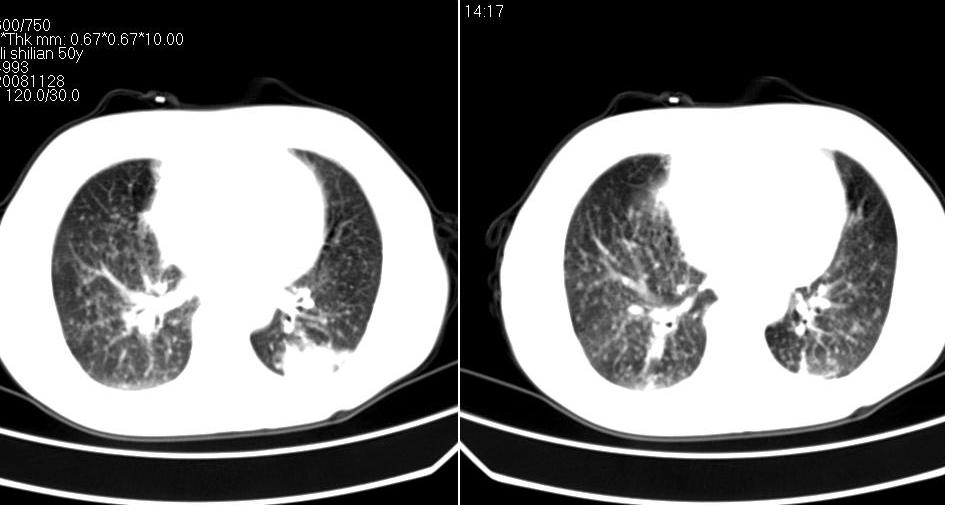

标题: CT16839:胸部CT平扫

女 50岁,在其他医院确诊肺癌.

肺癌并肺及纵隔转移

支持 右肺上叶肺癌并两肺及纵隔转移。

肺癌并肺内及纵隔淋巴结转移